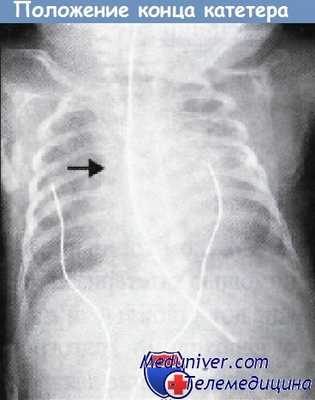

Рентгенограмма грудной клетки с кончиком катетера в правильном положении чуть выше места впадения верхней полой вены в правое предсердие.